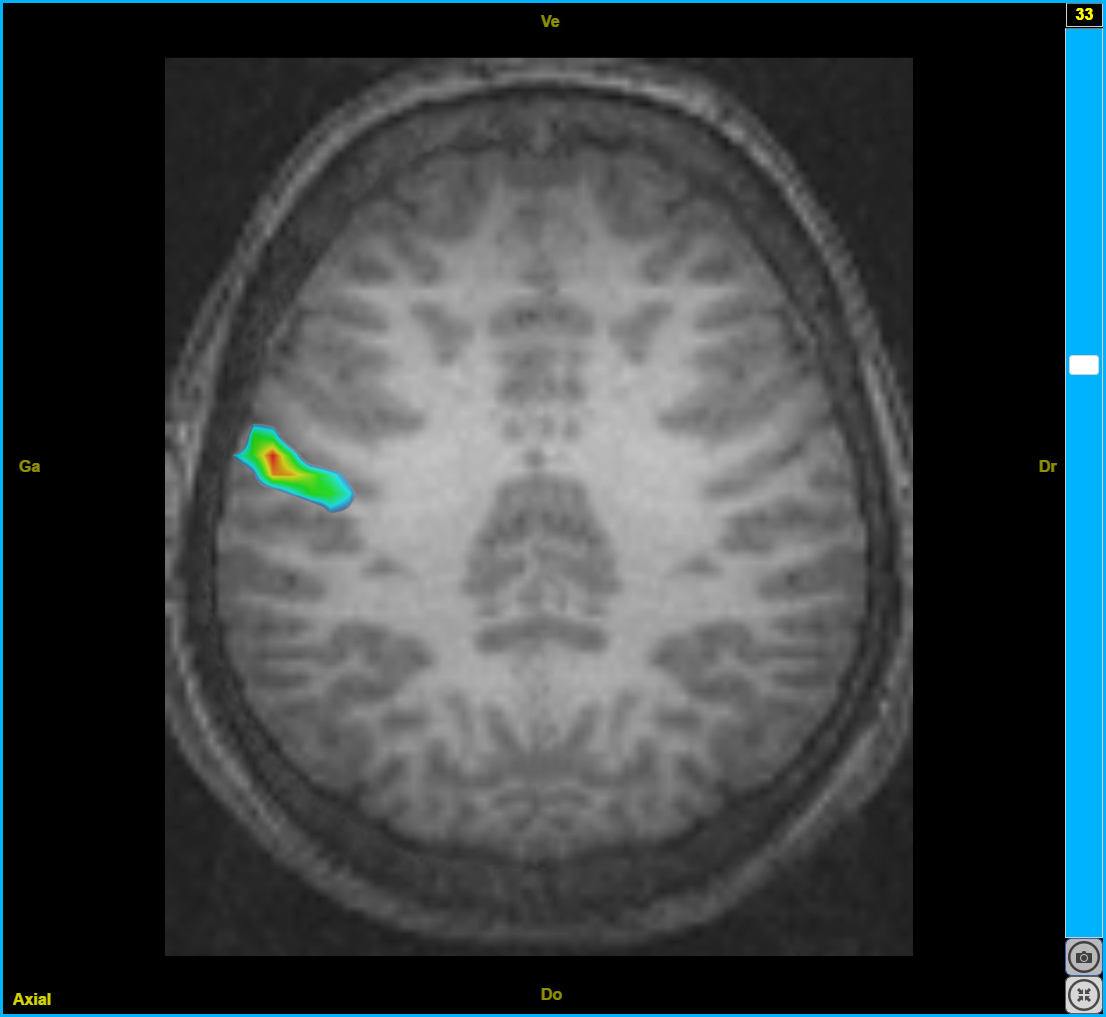

plasti6

Image dans sa taille originale :

213 ko